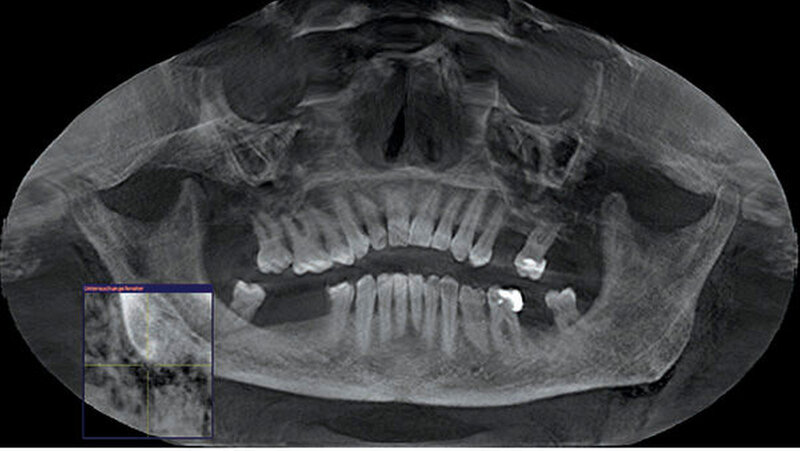

Zum Ausschluss einer Mittelgesichtsfraktur bei palpatorischem Weichteilemphysem erfolgte zur weiteren Diagnostik eine DVT-Aufnahme. Es zeigten sich keine Frakturen im Bereich des Mittelgesichts oder der Kiefer. Jedoch kam in der DVT-Bildgebung sowie der OPT-Optik ein massives Weichgewebeemphysem zur Darstellung (Abbildungen 2 bis 5).